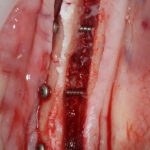

Подготовка костного ложа и фиксация аутотрансплантата

Возвращаемся к основной операционной области. Еще раз посмотрим на альвеолярный гребень, поофигеваем от его ширины и моих грандиозных планов:

Я зафиксировал костный блок практически без адаптации на несколько винтов. Обрати внимание, что винты находятся в зоне, где не планируется установка имплантатов. Фиксация должна быть надежной, поскольку мне еще предстояла подготовка лунок для имплантатов. Трех винтов для этого вполне достаточно.

Дальнейшая адаптация костного блока свелась к сглаживанию острых краев. После чего я приступил к подготовке лунок и установке имплантатов.